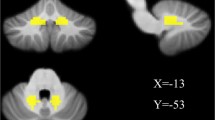

Brain maps for inter-group differences in the DN functional connectivity. The statistical threshold was set at p < 0.05 and cluster size >1080 mm3, which corresponds to a corrected p < 0.02. Warm colors illustrate regions showing higher functional connectivity in the former group. a Comparison between the TD and HC groups. b Comparison between the TD and NTD groups. c Comparison between the NTD and HC groups. For the details of the regions, see Table 2

Compared to the NTD group, the TD patients displayed higher functional connectivity of the bilateral DN with the left inferior temporal gyrus, the bilateral cerebellar anterior and posterior lobes, as well as lower functional connectivity between the bilateral DN with the bilateral prefrontal cortex, and the right superior parietal lobule (p < 0.02, corrected) (Table 2; Fig. 4).

In comparison between the NTD and HC groups, NTD group had higher DN functional connectivity with the right inferior frontal gyrus and the left superior temporal gyrus, and had lower DN functional connectivity with the left cerebellar posterior lobe, the right prefrontal cortex, the left caudate, and the left fusiform gyrus compared to the HC group.

Compared to the controls, the TD patients exhibited higher functional connectivity between the bilateral DN and the bilateral cerebellar anterior lobe, the left inferior temporal lobe, the right inferior frontal lobe, and the right parahippocampal, as well as lower functional connectivity between the bilateral DN and the left caudate, the right thalamus, the bilateral prefrontal cortex, and the right superior parietal lobule (p < 0.02, corrected) (Table 2; Fig. 4).